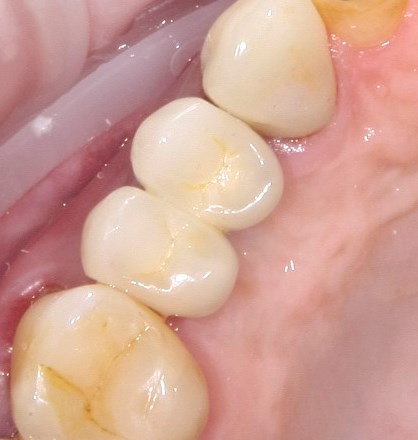

Опыт применения коллагеновой матрицы Mucograft в клинической практике.